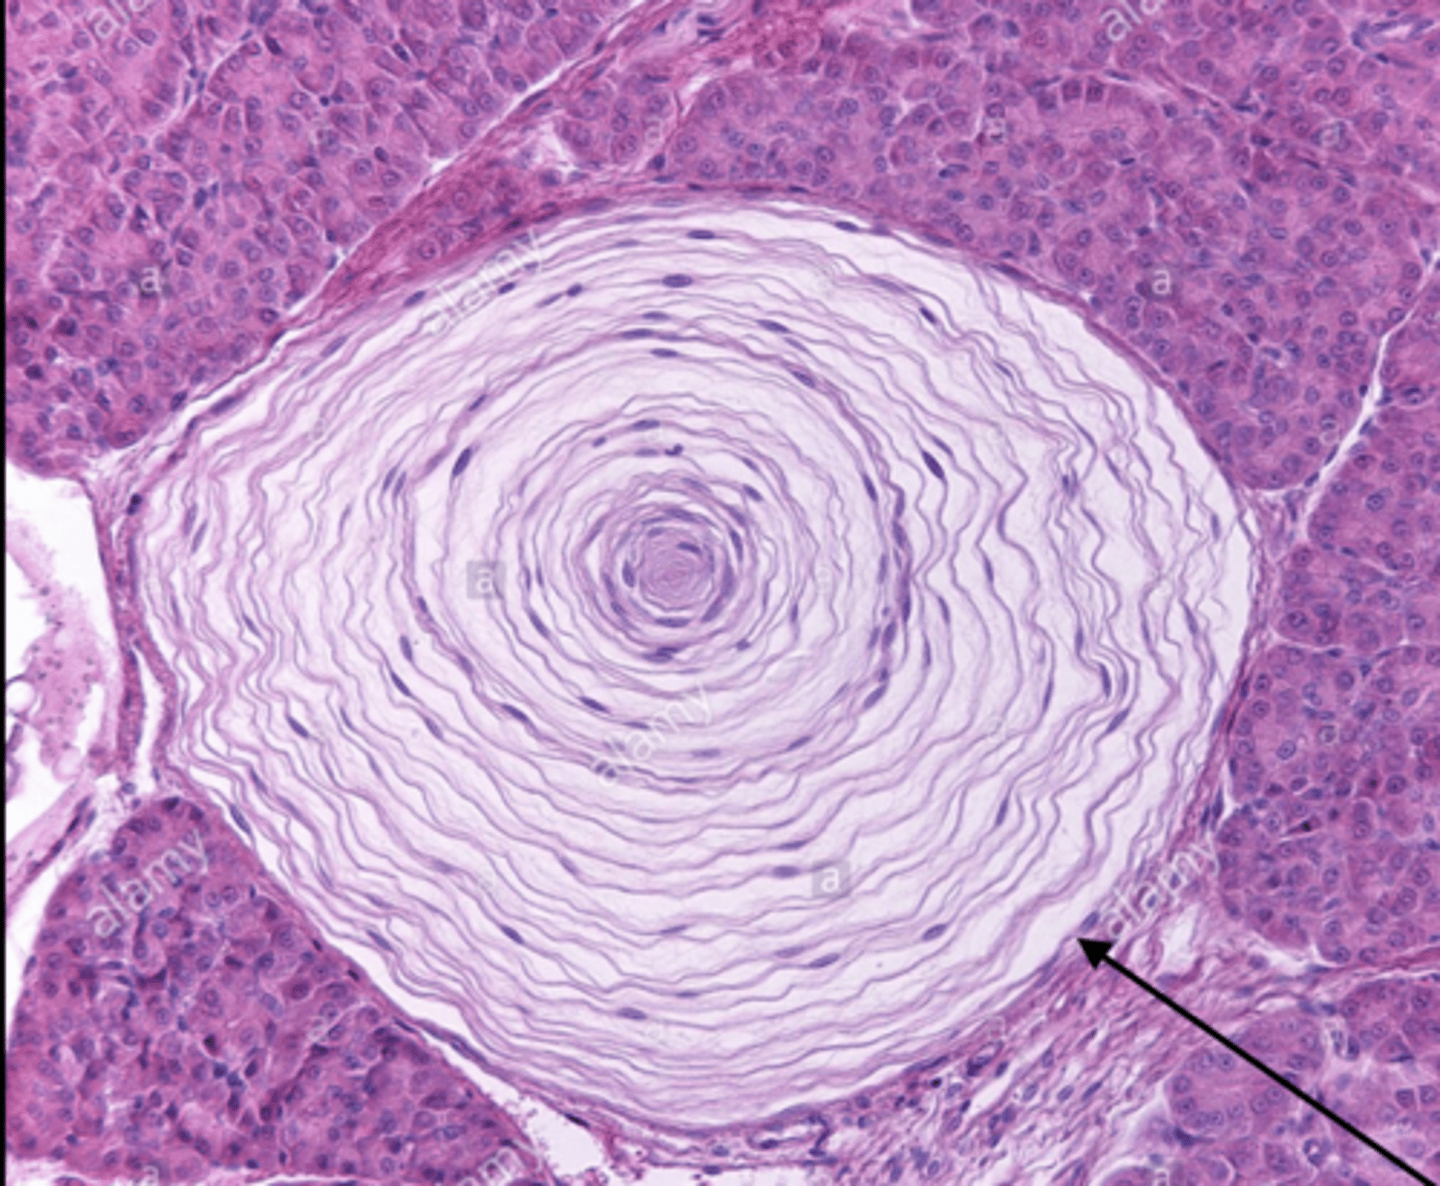

10

New cards

Tactile corpuscles (Meissner's corpuscles)

what is this called?

<p>what is this called?</p>

11

Lamellated corpuscles (Pacinian corpuscles)